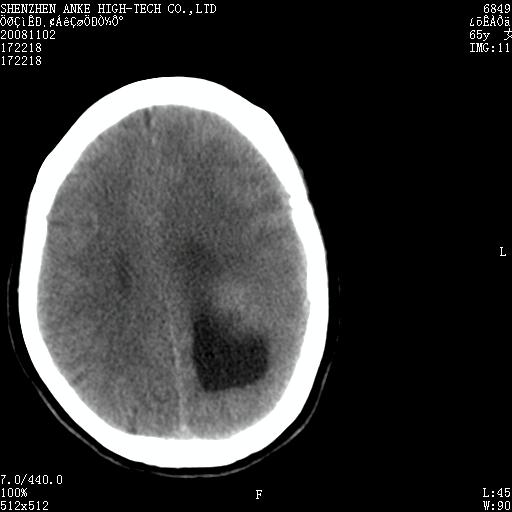

患者,女性,65岁,突发右侧肢体无力伴头痛,恶心、呕吐3小时.

1 左侧顶区圆形病灶,内可见钙化,考虑脑膜瘤,建议增强。2 左侧侧脑室病变,考虑神经上皮囊肿。

1)左侧顶区脑膜瘤可能性大;建议必要时行进一步检查。2)左侧脑室积水。

左顶部脑膜瘤,左侧侧脑室蛛网膜囊肿,建议增强.

左侧脑外占位(脑膜瘤)压迫脑实质、脑室侧室孔所致积水。支持!